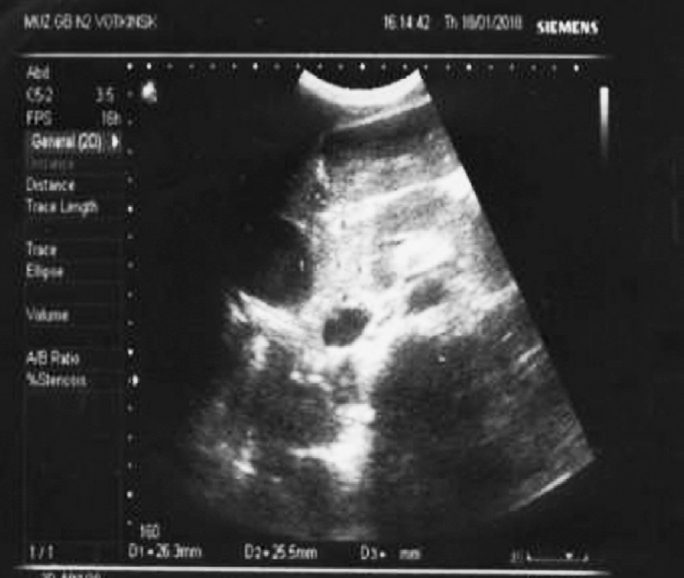

Аутоиммунный панкреатит — особая, своеобразная и относительно новая форма хронического панкреатита, которую в последние годы интенсивно изучают панкреатологи всего мира. Аутоиммунный панкреатит не имеет свойственной только ему клинической картины. Это состояние было впервые описано у взрослых и часто имитирует рак поджелудочной железы. Может поражать несколько органов, синхронно или метахронно, и редко встречается у детей. Представляет собой системное фибровоспалительное состояние с неясным патофизиологическим механизмом, влияющее на различные части тела. При отсутствии лечения заболевание может привести к фиброзу и необратимому повреждению органов, однако сочетание присущих аутоиммунному панкреатиту серологических, гистологических признаков и данных инструментальных методов исследования позволяет установить его наличие. IgG4-ассоциированное заболевание в основном описано у взрослых, поэтому педиатры обычно мало знают о нем. Мы подчеркиваем сложность диагностики аутоиммунного панкреатита — заболевания, связанного с IgG4, у детей. В статье представлены два клинических случая с детьми, которым был диагностирован аутоиммунный панкреатит. У обоих детей наблюдались симптомы абдоминальной боли и/или механической желтухи в сочетании с очаговым увеличением поджелудочной железы, неровностями основного протока поджелудочной железы и дистальным сужением. Согласно нашим данным, диагноз аутоиммунного панкреатита у детей может быть установлен на основе комбинации конкретных клинических симптомов при поступлении и различных результатов визуализации. Своевременно поставленный диагноз и начатое лечение является благоприятным прогнозом для дальнейшего течения данного заболевания и развития осложнений.